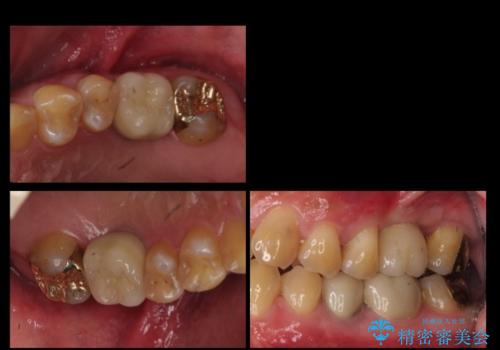

インプラントの向かい合わせの歯や隣の歯の虫歯治療も併せて行なっています。

同時期に治療することで咬み合わせの調整がしやすく、また、適合の良いものを作成できるメリットがあります。

左上7・左下7:PGAインレー 各6万円

左下5:仮歯 1万円、ジルコニアクラウン10万円、ファイバーコア 2万円

左下6:仮歯1万円、ジルコニアクラウン10万円

クラウンは全てスタンダードです。